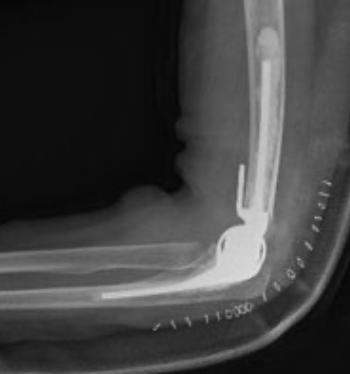

Endoprothetik des Ellenbogens

Bei schwerem Verschleiß

mit zerstörten Gelenkstrukturen:

- Teilprothesen.

- Vollprothesen.

Künstliches Gelenk

Bei fortgeschrittener Arthrose oder starker rheumatischer Zerstörung:

Endoprothese als funktionelle Dauerlösung.

Ellenbogenprothese